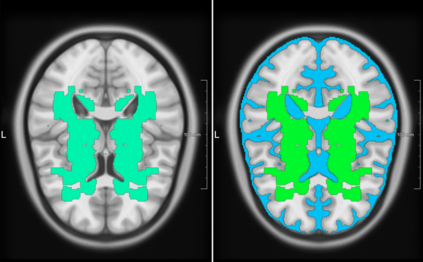

Lacunes of presumed vascular origin are fluid-filled cavities of between 3 - 15 mm in diameter, visible on T1 and FLAIR brain MRI. Quantification of lacunes relies on manual annotation or semi-automatic / interactive approaches; and almost no automatic methods exist for this task. In this work, we present a two-stage approach to segment lacunes of presumed vascular origin: (1) detection with Mask R-CNN followed by (2) segmentation with a U-Net CNN. Data originates from Task 3 of the "Where is VALDO?" challenge and consists of 40 training subjects. We report the mean DICE on the training set of 0.83 and on the validation set of 0.84. Source code is available at: https://github.com/hjkuijf/MixLacune . The docker container hjkuijf/mixlacune can be pulled from https://hub.docker.com/r/hjkuijf/mixlacune .